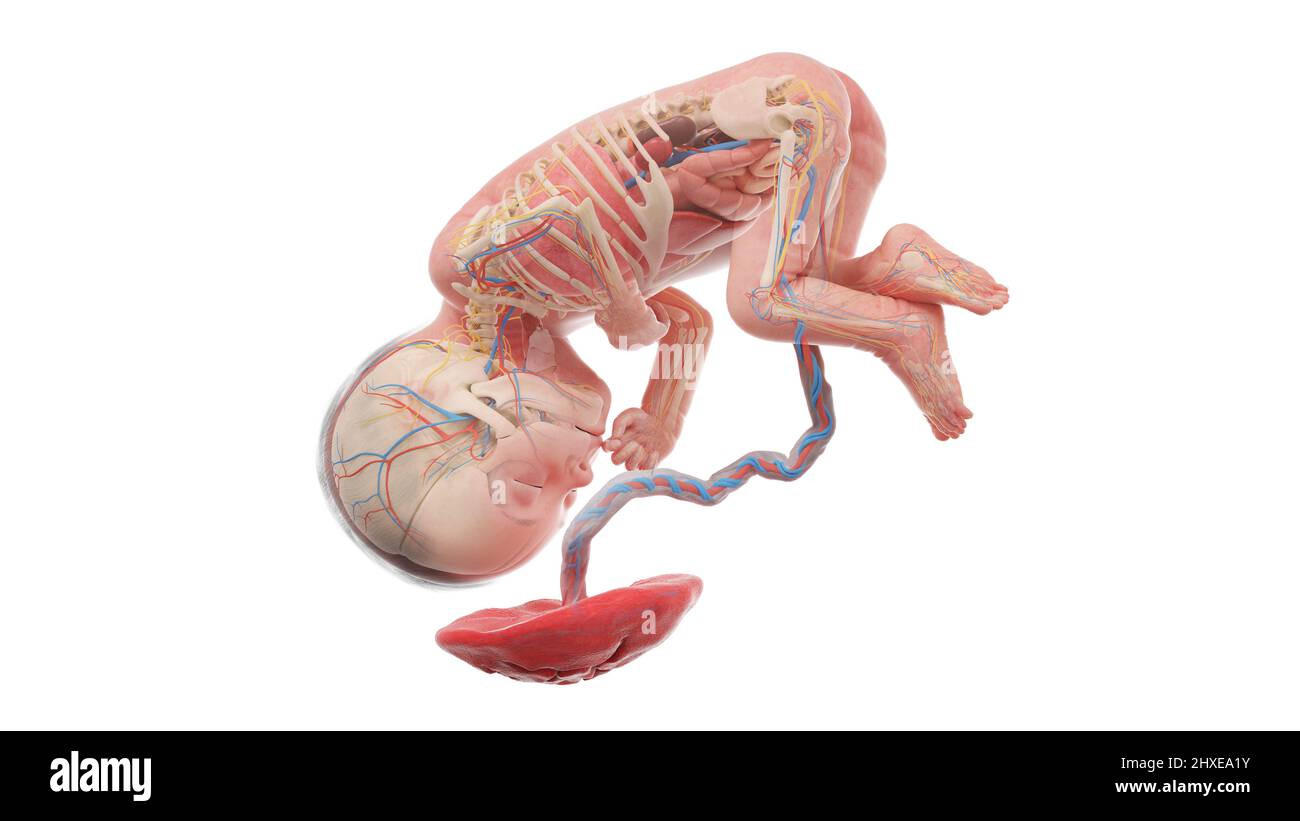

Anatomia del feto umano alla settimana 27, illustrazione Foto Stockhttps://www.alamy.it/image-license-details/?v=1https://www.alamy.it/anatomia-del-feto-umano-alla-settimana-27-illustrazione-image463765847.html

Anatomia del feto umano alla settimana 27, illustrazione Foto Stockhttps://www.alamy.it/image-license-details/?v=1https://www.alamy.it/anatomia-del-feto-umano-alla-settimana-27-illustrazione-image463765847.htmlRF2HXEA1Y–Anatomia del feto umano alla settimana 27, illustrazione